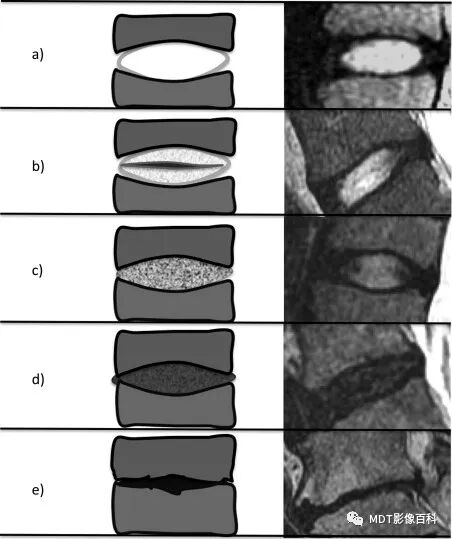

椎间盘退变的Pfirrmann分级系统

Pfirrmann分级系统是利用MRI对腰椎间盘退变进行分级的可靠分类系统。根据椎间盘信号强度、椎间盘结构、核与环之间的区别以及椎间盘高度,将退行性变分为5个等级。

2.椎间盘膨出

变性椎间盘的纤维环完整,超出椎体终板的边缘或向后膨突部分不超过4mm。矢状面见变性的椎间盘向后膨出,呈现出凸面向后的弧形改变的低信号。横断面见椎间盘对称地超出椎体终板边缘,无局限性突出。椎间盘膨出的特点是高信号的髓核未突出于低信号的纤维环之外。

3.椎间盘突出

高信号的髓核突出于低信号的纤维环之后,其突出部分仍与髓核母体相连。突出的髓核呈中等强度信号,边缘清楚,位于椎管中央或偏一侧,压迫硬膜囊。突出椎间盘的信号在T1加权像高于脑脊液,低于硬膜外脂肪;在T2加权像低于脑脊液,高于脊髓,与硬膜外脂肪相似。

当突出髓核穿过后纵韧带时,在矢状面上可显示其与未突出的部分“狭颈”相连征象;当突出的椎间盘体积较大时,硬膜囊受压变形。硬膜囊受压的深度在T2加权像显示较好,反映椎间盘突出的间接征象,但突出的直接征象在T1加权像显示明显。

4.髓核游离

高信号的髓核突出于低信号的纤维环之外,其突出部分与髓核母体不相连。突出物可位于原椎间隙水平,也可向上或向下迁移,其范围可达10mm左右。

膨出

突出

脱出

游离